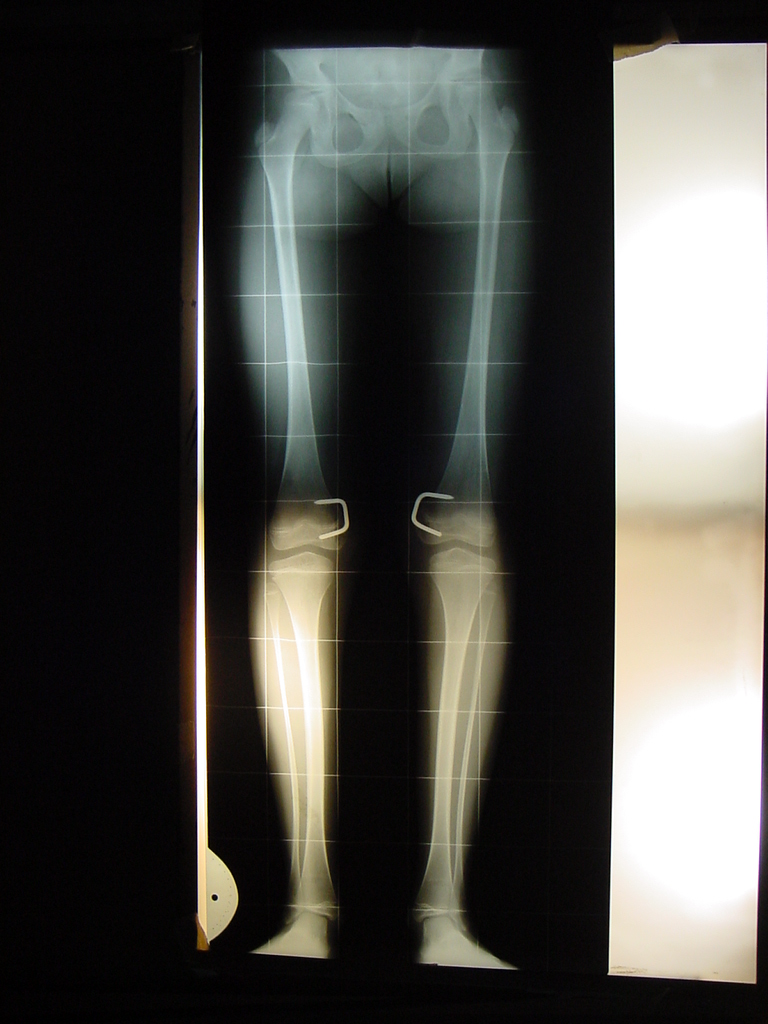

Modulación del crecimiento en osteodistrofia renal. [Growth modulation in renal osteodystrophy]

4. Oppenheim WL, Fischer SR, Salusky IB. Surgical correction of angular deformity of the knee in children with renal osteodystrophy. J Pediatr Orthop 1997;17:41-9.

5. Castañeda P, Urquhart B, Sullivan E, Haynes RJ. Hemiepiphysiodesis for the correction of angular deformity about the knee. J Pediatr Orthop 2008;28(2):188-91.

14. Stevens P, Klatt JB. Guided growth for pathological physes: radiographic improvement during realignment. J Pediatr Orthop 2008;28(6):632-9.